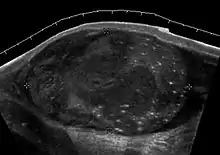

Fig. 23. Tubular ectasia of the testis. Honey-comb shaped cystic lesion at mediastinum testis.

Fig. 24. Tubular ectasia of the testis . Lesion in the testis mimicking testicular tumor, but the microcystic appearance of this lesion is suggestive of tubular ectasia.

The normal testis consists of several hundred lobules, with each lobule containing several seminiferous tubules. The seminiferous tubules of each lobule merge to form the straight tubes, which in turn converge to form the rete testis. The rete testis tubules, which lie within the mediastinum testis, are an anastomosing network of irregular channels with a broad lumen, which then empties into the efferent ductules to give rise to the head of the epididymis. Obstruction in the epididymis or efferent ductules may lead to cystic dilatation of the efferent ductules, which usually presents as an epididymal cyst on ultrasound. However, in the more proximal portion this could lead to the formation of an intratesticular cyst or dilatation of the tubules, so called tubular ectasia. Factors contributing to the development of tubular ectasia include epididymitis, testicular biopsy, vasectomy or an aging process. Clinically this lesion is usually asymptomatic. The ultrasound appearance of a microcystic or multiple tubular-like lesions located at the mediastinal testis [Fig. 23] and associated with an epididymal cyst in a middle-aged or elderly patient should alert the sonographer to the possibility of tubular ectasia. The differential diagnosis of a multicystic lesion in testis should include a cystic tumor, especially a cystic teratoma. A cystic teratoma is usually a palpable lesion containing both solid and cystic components; and the cysts are normally larger than that of tubular ectasia, which appear microcystic [Fig. 24]. Furthermore, the location of tubular ectasia in the mediastinum testis is also helpful in making the differential diagnosis.